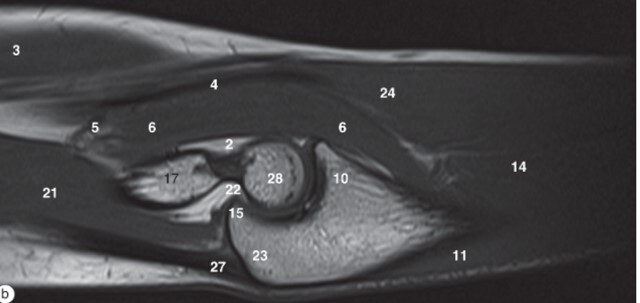

Label 3,6,9,17,21,23,28

3=Biceps brachii muscle

6-Brachialis muscle

9=Coronoid process

17=Humerus

21=Triceps brachii

23=Olecranon process of ulna

28-Trochlea of humerus